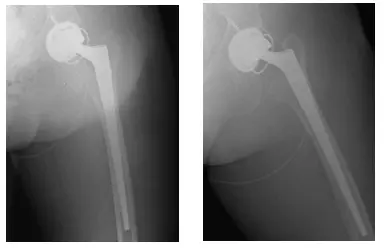

Radiografías postoperatorias de caderas bilaterales

Las radiografías muestran una THA izquierda con un liner constreñido

Tras el seguimiento, la paciente se encontraba mucho mejor y ya no sufría luxaciones de la cadera izquierda. En el último seguimiento, el paciente no tenía dolor, soportaba peso según lo toleraba y tenía una buena amplitud de movimiento.